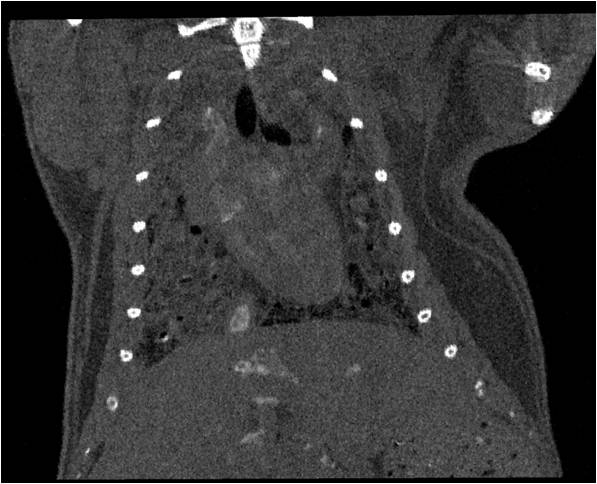

腫瘤血管生成

心血管

胸部和心血管的層析成像 胸部和心血管的3D圖像